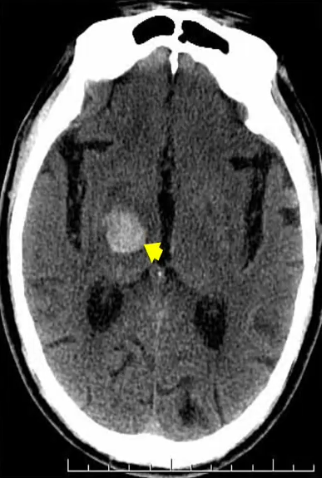

CT表现:

急性期丘脑血肿常表现为丘脑内圆形、类圆形或不规则形高密度影,边界清楚或边缘可见窄带样低密度影围绕,邻近结构(如内囊、侧脑室三角区、第三脑室)可见不同程度的受压变形。由于丘脑血肿邻近第三脑室与侧脑室,故常可见丘脑血肿从邻近脑室缘破入侧脑室或第三脑室。